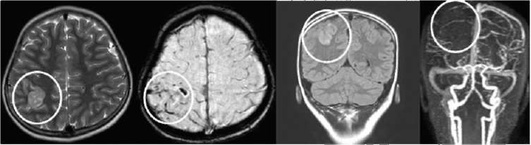

image

Рис. 5-7. Компьютерные томограммы в аксиальной проекции в «мозговом» окне. Течение острого нарушения мозгового кровообращения по ишемическому типу в левом полушарии большого мозга у ребенка 7 лет

Рис. 5-8. Организация геморрагического инсульта по данным компьютерной томографии. Феномен «тающего кусочка сахара» - от периферии к центру гематомы. В 1-3 сут наблюдается гиперденсивный очаг с четкими контурами, затем на 7-10 сут очаг начинает уменьшаться от периферии к центру, контуры его становятся нечеткими и спустя 2-3 нед, в зависимости от объема гематомы, гиперденсивный очаг практически не визуализируется (изоденсивная зона). По периферии гематомы определяется гиподенсивная зона перифокальных изменений